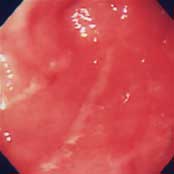

慢性胃炎:

胸やけ、もたれ、むかつきを訴えて来院。内視鏡で観察してもわずかに線状の発赤を認めるのみで、慢性胃炎の一種の表層性胃炎の所見です。このような慢性胃炎の方の中に、なかなか治らない胸やけ、もたれ、むかつきに悩まれている方が多くいます。機能的上部消化管症状と呼ばれ、胃や食道の正常な運動機能の衰えが原因です。抗潰瘍剤や粘膜保護剤では効果が少なく、消化管運動促進剤を内服すると改善します。